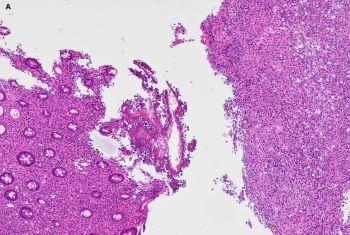

65 yo male with history of bone marrow tx for multiple myeloma presents with abdominal pain and diarrhea. Colonoscopy showed inflamed mucosa with ulcerations and polypoid lesions.

The correct answer is: C. Disseminated Histoplasmosis.

Microscopically, Histoplasma appears as ovoid fungal organisms with narrow based budding. H. capsulatum variant capsulatum is roughly 2-4 micrometers in length. Histoplasma capsulatum variant duboisii is endemic to Africa, 6 to 12 micrometers, and can appear spherical. Organisms can often be found in macrophages and associated with granulomatous inflammation. Microscopic diagnosis can be made from tissue sections (H&E and special stains such as GMS and PAS) as well as microscopy of body fluids like bronchoalveolar lavage specimens. The gold standard for diagnosis is microscopic recognition in tissue/body fluid specimens as well as culture at room temperature. Supportive laboratory studies include urine Histoplasma antigen testing (most sensitive in disseminated and acute pulmonary cases), antibody serologic testing (not as useful for acute cases), and PCR based assays (variable sensitivity/specificity and no current FDA approved assays).